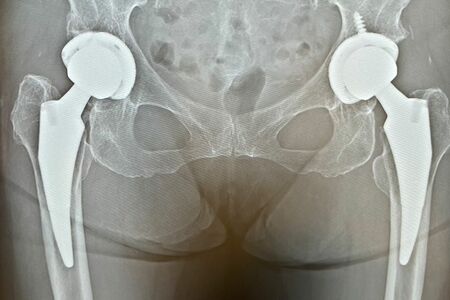

こうして76歳のときに両側の人工股関節置換術を受ける。同じ病気に悩む人の参考になればと術後の経過をブログに書き始めると、医師であり患者でもある意見は説得力があると徐々に読者が増えていった。